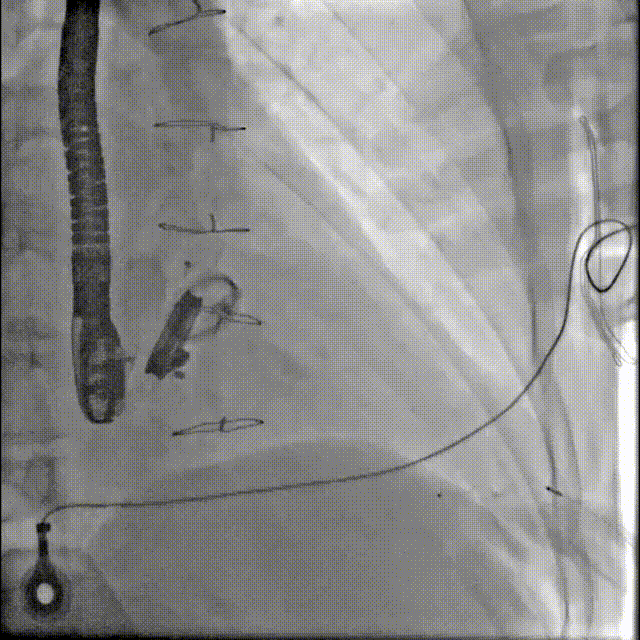

1.患者平卧位,食道超声检查瓣周漏位置及大小,并引导穿刺心尖,选择7F鞘管通过10点位置瓣周漏口,将单弯导管送入左心室,置换超硬导丝至左心室,选择12-14mmPDAO封堵10点位漏口。

3.选择7F鞘管通过1-2点位置瓣周漏,彩超显示鞘管对瓣周漏口的影响较小,结合漏口大小,选择14-16mmPDAO封堵此处漏口。

术后封堵器形态位置